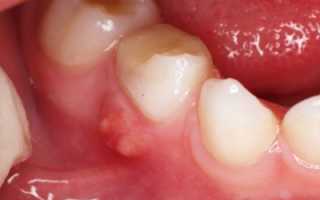

Гранулёма: что это такое

Напоминает небольшой мешочек (около 0,5 см), окружённый грануляционной тканью, как капсулой. Внутри — воспалительная жидкость. Место расположения — верхушка зуба. Это эпицентр заболевания. Задача такого осложнения: разрушить здоровую ткань зуба. Воспалительный очаг нельзя оставлять без лечения, так как дальнейшее бездействие приведёт к нарушению многих систем организма.

Фото 4. Гранулёма, возникшая из-за периодонтита. Представляет из себя припухлость на десне.